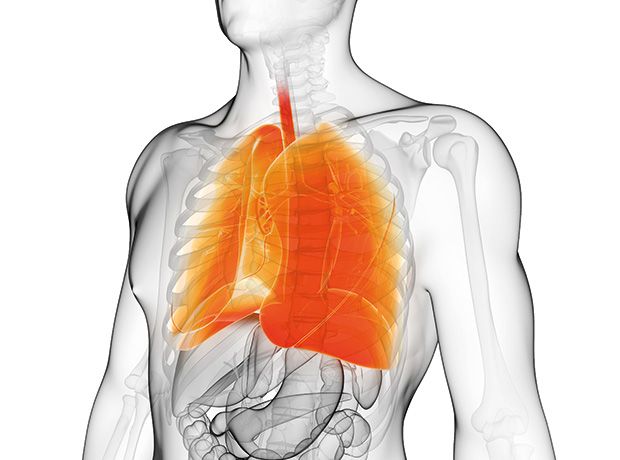

嘿,朋友们,今天咱们得聊聊一个听起来就让人皱眉头的话题——肺炎克雷白杆菌肺炎。这可不是什么小感冒,它可是个狠角色,专门瞄准我们的肺部,搞得我们咳嗽不止,喘息连连。

想象一下,你的肺,那可是你呼吸的发动机啊,突然间被这些看不见的小家伙给占领了,你的身体就成了它们的战场。那种感觉,就像是有人在你的胸口上压了一块大石头,让你喘不过气来。这种肺炎,可不是随便吃点药就能好的,它需要我们全力以赴,才能把那些讨厌的家伙赶出去。

而且,这事儿还挺挑人的,年纪大点的,身体本来就不太好的,更容易被它盯上。所以啊,我们得提高警惕,平时多注意身体,别让它有机可乘。